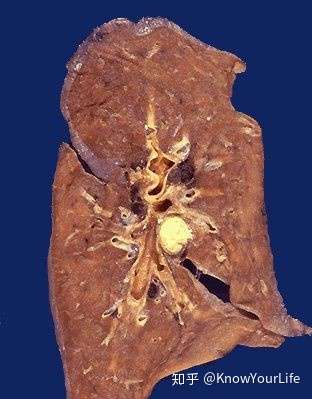

肺干酪样坏死

肺中间的黄色部分就是干酪样坏死